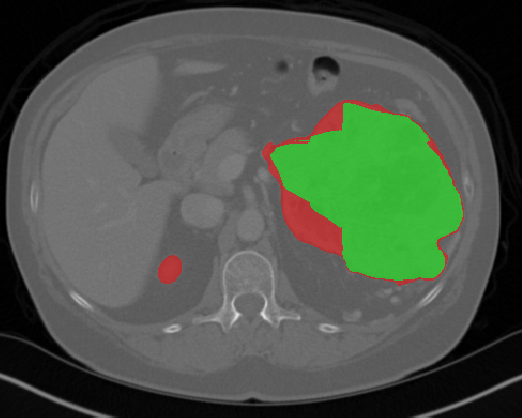

Edge-Aware 3D Image Segmentation Networks

[91]: Automated segmentation of kidneys and kidney tumors is an important step in quantifying the tumor’s morphometrical details to monitor the progression of the disease and accurately compare decisions regarding the kidney tumor treatment. Manual delineation techniques are often tedious, error-prone and require expert knowledge for creating unambiguous representation of kidneys and kidney tumors segmentation. We propose a 3D end-to-end edge-aware FCN for reliable kidney and kidney tumor semantic segmentation from arterial phase abdominal 3D CT scans. Our segmentation network consists of an encoder-decoder architecture that specifically accounts for organ and tumor semantics. We evaluate our model on the 2019 MICCAI KiTS Kidney Tumor Segmentation Challenge dataset. -

Kidney and Kidney Tumor Segmentation

Kidney cancer accounted for nearly 175,000 deaths worldwide in 2018 [13], and it is projected that 14,770 deaths will occur due to the disease in 2019 in the US [111]. Current kidney tumor treatment planning includes Radical Nephrectomy (RN) and Partial Nephrectomy (PN). In RN, both the tumor and the affected kidney are removed whereas in PN the tumor is removed but kidneys are saved [116]. Although RNs were historically prevalent as a standard treatment procedure for kidney tumors, new capabilities for earlier detection of the tumors as well as advancements in surgery has made PNs a viable treatment approach [53].

Traditionally, various techniques such as deformable models [86], GrabCuts, region growing and atlas-based methods have been applied to the problem of kidney segmentation. In recent years, researchers have attempted to leverage the power of deep learning and CNNs to build segmentation frameworks that are more automated and less dependant on incorporation of prior shape statistics. Thong et al. [119] proposed a 2D patch-based approach for kidney segmentation in contrast-enhanced CT scans by leveraging a modified ConvNet.

Jackson et al. [62] developed a framework for detection and segmentation and of kidneys in non-contrast CT images by utilizing a 3D U-Net. Yang et al. [128] proposed a method for kidney and renal tumor segmentation in CT angiography images by a modified residual FCN that is equipped with a pyramid pooling module. Furthermore, Yin et al. [130] employed a cascaded approach for segmentation of kidneys with renal cell carcinoma by training a CNN that predicts a bounding box around the kidney and a subsequent CNN that segments the kidneys. Recently, Xia et al. [126] proposed a two-stage approach for the segmentation of kidney and space-occupying lesion areas by using SCNN and ResNet for image retrieval and SIFT-flow and MRF for smoothing and pixel matching.